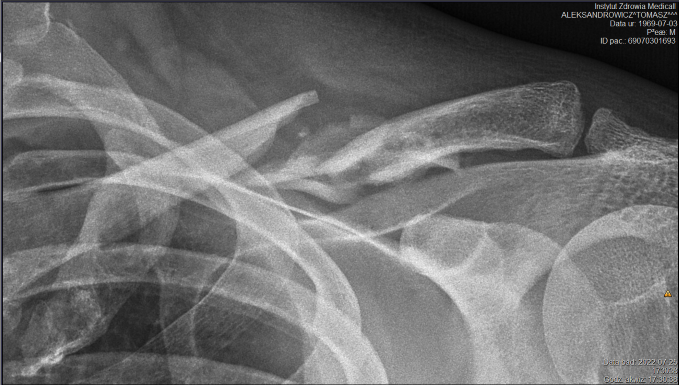

Na zdjęciu przed i po operacji.